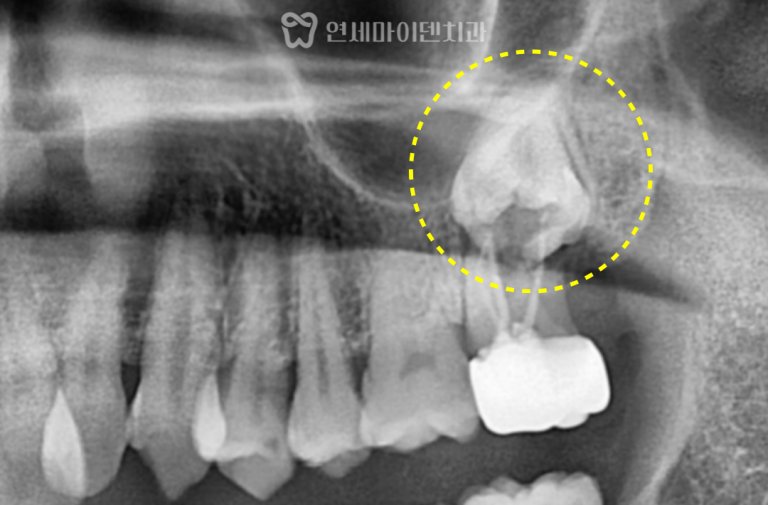

발치 즉시 임플란트 증례: 매복 사랑니 발치 치료 난이도가 높은 사례 중에서도특히 매복 사랑니와 연관된 최후방…